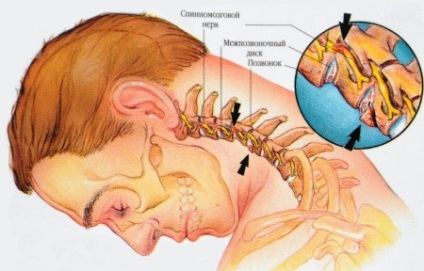

Sérv nyaki gerinc porckorong betegség diagnózisa

Sérv a nyaki gerinc újabban vált meglehetősen gyakori, ez nagyrészt a számának növekedése az irodai dolgozók, a munkanap, amely zajlik a számítógép szék, az általános visszaesés a fizikai aktivitás a lakosság körében. Porckorongsérv lemezek a nyaki gerinc (AIZ) kötelező legyen a kezelés annak a ténynek köszönhető, hogy a komplikációk fogyatékosság jogokat.

Leggyakrabban a betegek, akik jönnek az orvos panaszkodik a fájdalom a nyak, a vállöv. Első időszakos fájdalom szindróma enyhe sajgó lokalizált a nyak hátsó egyidejű feszültség paravertebralis izmokat. A fájdalom lehet súlyosbítja hajlítás a fej előre, balra és jobbra mozog, tüsszögés és köhögés.

Amellett, hogy a fájdalom betegek e patológia az ember van a következő tünetek:

- Feeling bizsergés a felső végtag és a vállöv, égő érzés ugyanazon a helyen.

- Izomgyengeség, zsibbadás a felső végtagok.

- Csökkentett érzékenysége a felső végtagok, amíg a teljes bénulás.

- Csökkentése és reflexkiesések a vizsgálatot.

- Szédülés, fülzúgás, fejfájás, csökkent koordináció mozgások.

Tudnia kell azt is, hogy a fájdalom közvetlenül kapcsolódik mind a pusztítás lemezterület, és a méret a sérv.